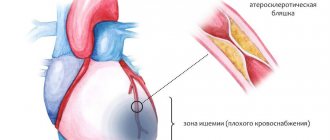

ИБС (МКБ-10 I20- I25) – это состояние, которое возникает вследствие нарушений притока артериальной крови к сердечной мышце на фоне закупорки коронарных сосудов или их спазма, и протекает в хронической или острой форме. Когда в сердце не поступает необходимого ему объема кислорода, в просветах мышечных волокон формируются участки соединительной ткани, утратившие способность полноценно функционировать. Процесс поражения сердечной мышцы всегда происходит с развитием незначительной ишемии, которая без соответствующей терапии со временем провоцирует возникновение истинного инфаркта.

) лежит стеноз коронарных артерий, который развивается в результате их поражения атеросклерозом. При хроническом нерезко выраженном стенозе больные в покое обычно не предъявляют жалоб.

Если стеноз

достигает 50% просвета артерии и более, появляются симптомы стенокардии, обусловленные несоответствием между потребностью миокарда в кислороде и доставкой его с коронарным кровотоком; вначале симптомы появляются только при физической нагрузке (стабильная стенокардия), а в дальнейшем, по мере прогрессирования стеноза, также в покое (нестабильная стенокардия).

В итоге при закупорке коронарной артерии развивается инфаркт миокарда

(ИМ) и, возможно, внезапная смерть (нестабильную стенокардию и ИМ объединяют в понятие «острый коронарный синдром»).

В патогенезе коронарного стеноза

важная роль принадлежит повреждению эндотелия коронарных артерий под влиянием различных сердечно-сосудистых факторов риска. Макрофаги, поглощая липидные отложения в интиме артерии, превращаются в пенистые клетки, которые участвуют в формировании ранних атеросклеротических изменений.

В дальнейшем образуется фиброзно-жировая бляшка

, а затем и фиброзно-мышечная бляшка, которая сужает просвет артерии. В результате надрывов интимы и разрыва бляшки, а также кровоизлияния в нее и тромбообразования происходит частичная или полная закупорка ее просвета. Клинически кровоизлияние в бляшку и тромбоз коронарной артерии проявляются ОКС.

Основная причина заболевания — кислородное голодание организма. Кислород перестает поступать по кровеносным сосудам, в результате сокращается питание клеток. Все это вместе нарушает нормальную работу сердца. Предвестником ишемии является атеросклероз кровеносных сосудов. Просветы сосудов начинают сужаться, а холестериновые бляшки образуются все чаще.